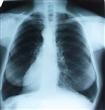

أظهرت الأبحاث الطبية أن تناول المدخنين لجرعات إضافية من فيتامين “د” يساعد في تأخير التدهور الذي تتعرض له رئة المدخنين خاصة بين المدخنين الذين يعانون من نقص في هذا الفيتامين. وأوضح الباحثون أنه على الرغم من الدور الذي يلعبه فيتامين “د” في تأخير التدهور الذي يطرأ على وظائف الرئة بين المدخنين إلا أنه لا يقي من فرص الإصابة بالسرطان وأمراض القلب والسكتات الدماغية. وأرجع الباحثون فاعلية فيتامين “د” في تأخير تدهور الرئة إلى خواصه المضادة للأكسدة والالتهابات تلعب دورا مهما في هذا التأخير.